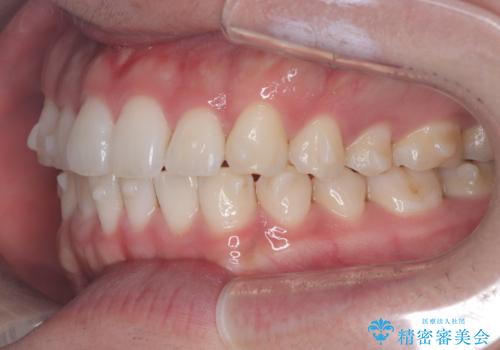

歯のデコボコを治したい|インビザラインで綺麗な歯並びに!|矯正期間は6ヵ月!

インビザラインで叢生の改善を行いました。

歯は抜かずに、拡大と少しのIPRで並べました。

矯正期間は半年です。

綺麗な歯並びを手に入れ大変ご満足していただきました。